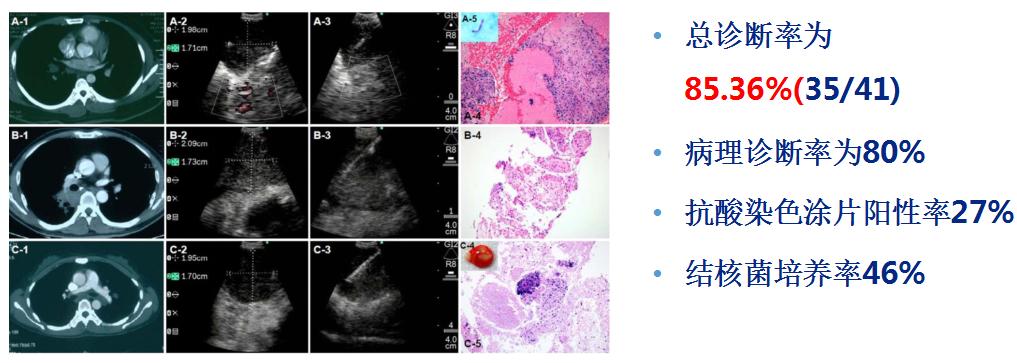

5.EBUS-TBNA诊断胸内良性疾病

(1)EBUS-TBNA诊断胸内结核